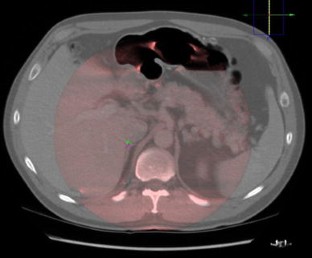

CBCT scans were acquired in the interventional suite (Philips Allura Xper FD20) and rigidly registered to the vertebra in previously acquired CE-CT. Adrenal vein locations were marked on the CT image and superimposed with live fluoroscopy and digital-subtraction angiography (DSA) to guide the AVS. Seventeen first attempts at AVS were performed with image registration and retrospectively compared with 15 first attempts without image registration performed earlier by the same 2 interventional radiologists. First-attempt AVS was considered successful when both adrenal vein samples showed representative cortisol levels. Sampling time, dose-area product (DAP), number of DSA runs, fluoroscopy time, and skin dose were recorded.

Fig. 1

Fig. 2